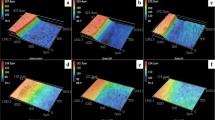

Using real-time 2D microradiographic analysis, a facilitated transport of dentinal fluid from the pulp chamber towards the PNEC was detected in 42.86% of the lesions, being statistically different from the expected proportion of 20% (p = 0.0081) with a medium effect size (Cohen H of 0.51), and power of 84.3%. In lesions with ICDAS score 3, the contrast solution (dentinal fluid) penetrated into the body of the PNEC (Fig. 2). In such lesions, profilometric analysis of surface changes in response to displacement of dentinal fluid revealed that all of the 4 lesions presented variations in surface height (in μm) after infiltration of the contrast solution into the pulp chamber (Fig. 3 and Supplemental Material Fig. 5).

Time-series images sequence (0 min, 5 min, 10 min, 15 min, 20 min, and 30 min) of changes in surface topography of PNEC after infiltration of Thoulet’s solution in the pulp chamber. Colors indicate variations in surface height (see color scale in A, which is valid for all images). Areas with the most pronounced surfaces changes are indicated by arrows.

Typical histological aspects of enamel and dentine reactions to caries of a PNEC lesion analyzed under microCT. (a,c and e) show images of a microCT scanning obtained before the biofilm experiment. (b,d and f) show images of the same tooth scanned after the biofilm experiment terminated and after a 24 h-infiltration of the contrast solution in the pulp chamber. Contrast solution evidenced a facilitated transport pathway from the pulp chamber across the dentine layer (arrows) up to the body of the PNEC. Reduction in the radiolucent PNEC area is shown after infiltration of the contrast solution.

During in vitro infiltration of Thoulet’s solution 1.47 (the same as our contrast solution) into ground sections of NEC, it has been shown that an intense displacement of air by the infiltrating solution is still occurring up to 2 h after immersion of NEC in the solution, and even after 24 h of immersion air is not completely replaced by the solution22. Thus, the replacement of air by Thoulet’s solution in NEC is expected to be a very slow process when the lesion is in this original physical presentation (within a whole crown as here). Such a relatively long duration process combined with the occurrence of surface layer in NEC with ICDAS score 1–2 renders only NEC with ICDAS score 3 suitable for profilometric analysis of surface changes in response to infiltration of dentinal fluid. The changes in surface height detected in our NEC lesions with ICDAS score 3 can be explained as a result of the penetration of dentinal fluid into the carious enamel pores, and then emerging on the NEC surface. These results raised the question on whether the dentinal fluid could interact with the biofilm fluid and affect the composition of a cariogenic biofilm formed in vitro on the NEC surface.